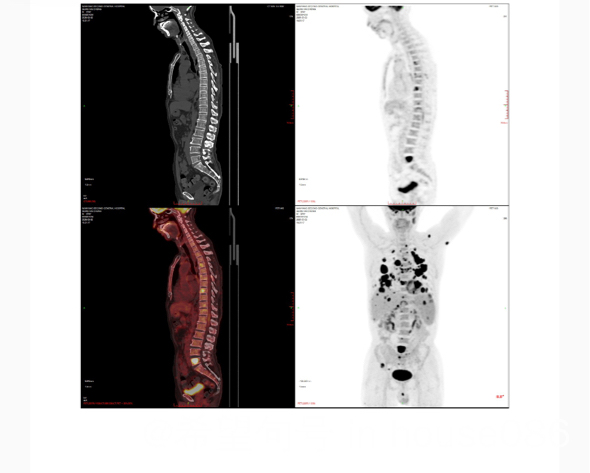

弥漫大B细胞淋巴瘤非发生中心型non-GCB型,74岁无基础疾病,骨髓未受累,全身多处器官受累,肺部七厘米大肿块,肝两厘米肿块,ki67/90➕,bcl2/90➕双表达,不排除双打击,基因突变等高危因素,有相似病友吗?治疗效果怎么样